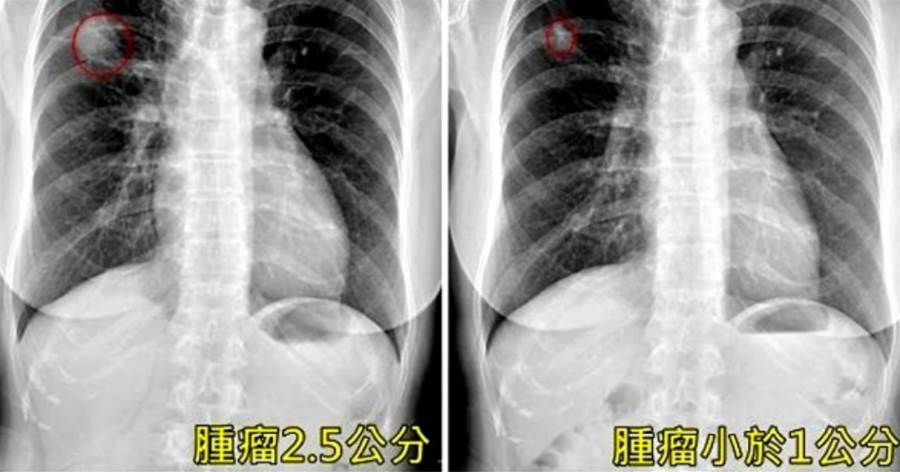

高敏敏指出,肺腺癌被稱為「沉默的殺手」,初期幾乎沒有明顯癥狀,往往發現時已屬中晚期。

高敏敏提醒,若出現長期咳嗽、食慾不振、體重下降、易疲倦、胸痛、呼吸急促等癥狀,務必提高警覺並儘早就醫,「早期發現、早期治療是關鍵,第一期的療愈率可高達八成以上」。